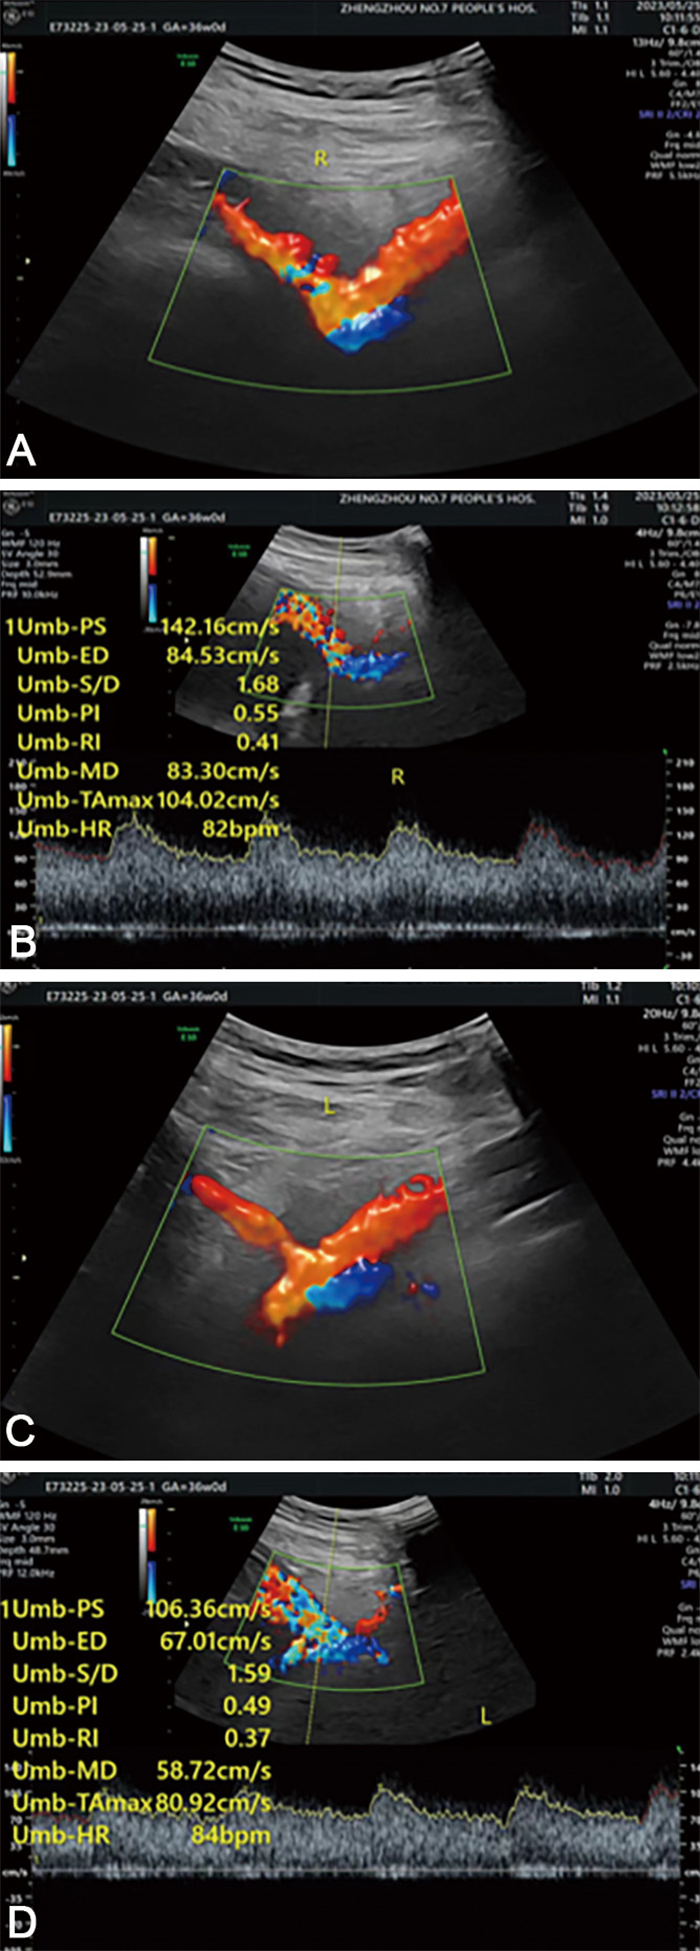

子宫动脉血流参数联合血清甲胎蛋白预测双胎早产应用分析

邢丽丽, 范淑玉, 喻红霞, 曹宁

2024, 22(11): 1917-1920. doi: 10.16766/j.cnki.issn.1674-4152.003764

765 6

摘要:

目的  早产(PTB)是新生儿死亡的主要原因,PTB风险较高的双胎孕妇胎盘屏障容易破裂,胎血流入母体,造成母体血清甲胎蛋白(AFP)水平升高。本研究探讨了子宫动脉血流参数联合AFP预测双胎早产的预测价值。  方法  选择2015年1月—2021年4月定期在郑州市第七人民医院产检的100例双胎妊娠孕妇进行回顾性分析,根据妊娠结局分为早产组(51例)和足月组(49例)。通过重复测量方差分析对比孕中期血清AFP水平和子宫动脉血流参数的差异,并且通过logistic回归分析研究二者对双胎妊娠早产结局的预测价值。  结果  随妊娠进展,早产组和足月组子宫动脉搏动指数(PI)、子宫动脉阻力指数(RI)、子宫动脉血流S/D值均逐渐下降,血清AFP水平均逐渐上升,早产组不同孕周子宫动脉血流动力学参数及血清AFP水平均高于同期足月组(P < 0.05)。血清AFP、PI、RI、S/D值及四者联合预测双胎早产的AUC分别为0.952、0.881、0.903、0.919和0.966。Logistic回归分析显示,血清AFP、PI、RI和S/D值是双胎孕妇早产的影响因素(OR值分别为2.746、1.262、1.509、2.158)。  结论  血清AFP水平、PI、RI和S/D值可以联合预测双胎早产,并且提高了单指标的灵敏度和特异度。